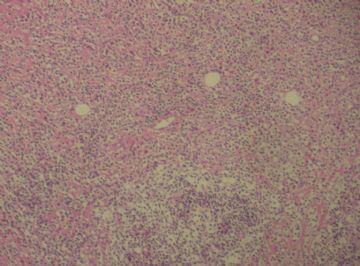

标本名称:  左前臂数个大小不等的皮下肿物。

既往有非何杰金淋巴瘤(滤泡性淋巴瘤)病史22个月。

• 左前臂数个大小不等的皮下肿物     淋巴瘤?图3

图3

病例不错。细胞胞浆透亮,间质血管丰富,图片不是很清晰,似乎有嗜酸粒细胞?

恶性,首先考虑T-NHL。IHC证实。

既往有NHL病史,图片不太清晰,细胞弥漫,胞浆透亮,首先考虑T细胞淋巴瘤。